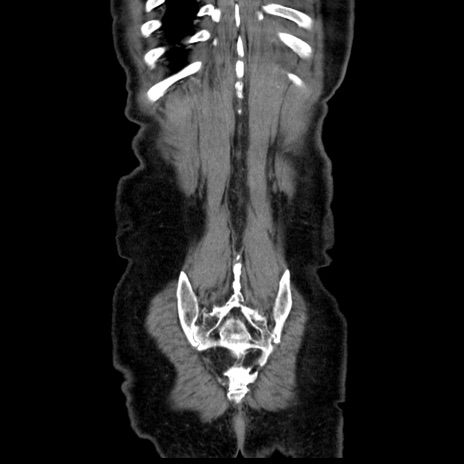

横断像